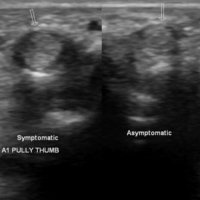

Thickening and hyper-vascularization of the A1 pulley are the hallmarks of trigger fingers on sonography. Other frequently observed features include distal flexor tendinosis and tenosynovitis.

The first annular pulley (A1) at the metacarpal head is by far the most often affected pulley in trigger finger, though cases of triggering have been reported at the second and third annular pulleys (A2 and A3, respectively), as well as the palmar aponeurosis.

The level of thickening can be variable with some authors suggesting the normal value being around 0.5 mm with thickening suggested when the diameter is over 1.1 mm.

The condition can be conservatively managed with splinting, NSAIDs, and local steroid injections or may require a surgical section of the A1 pulley when the pulley is markedly thickened.